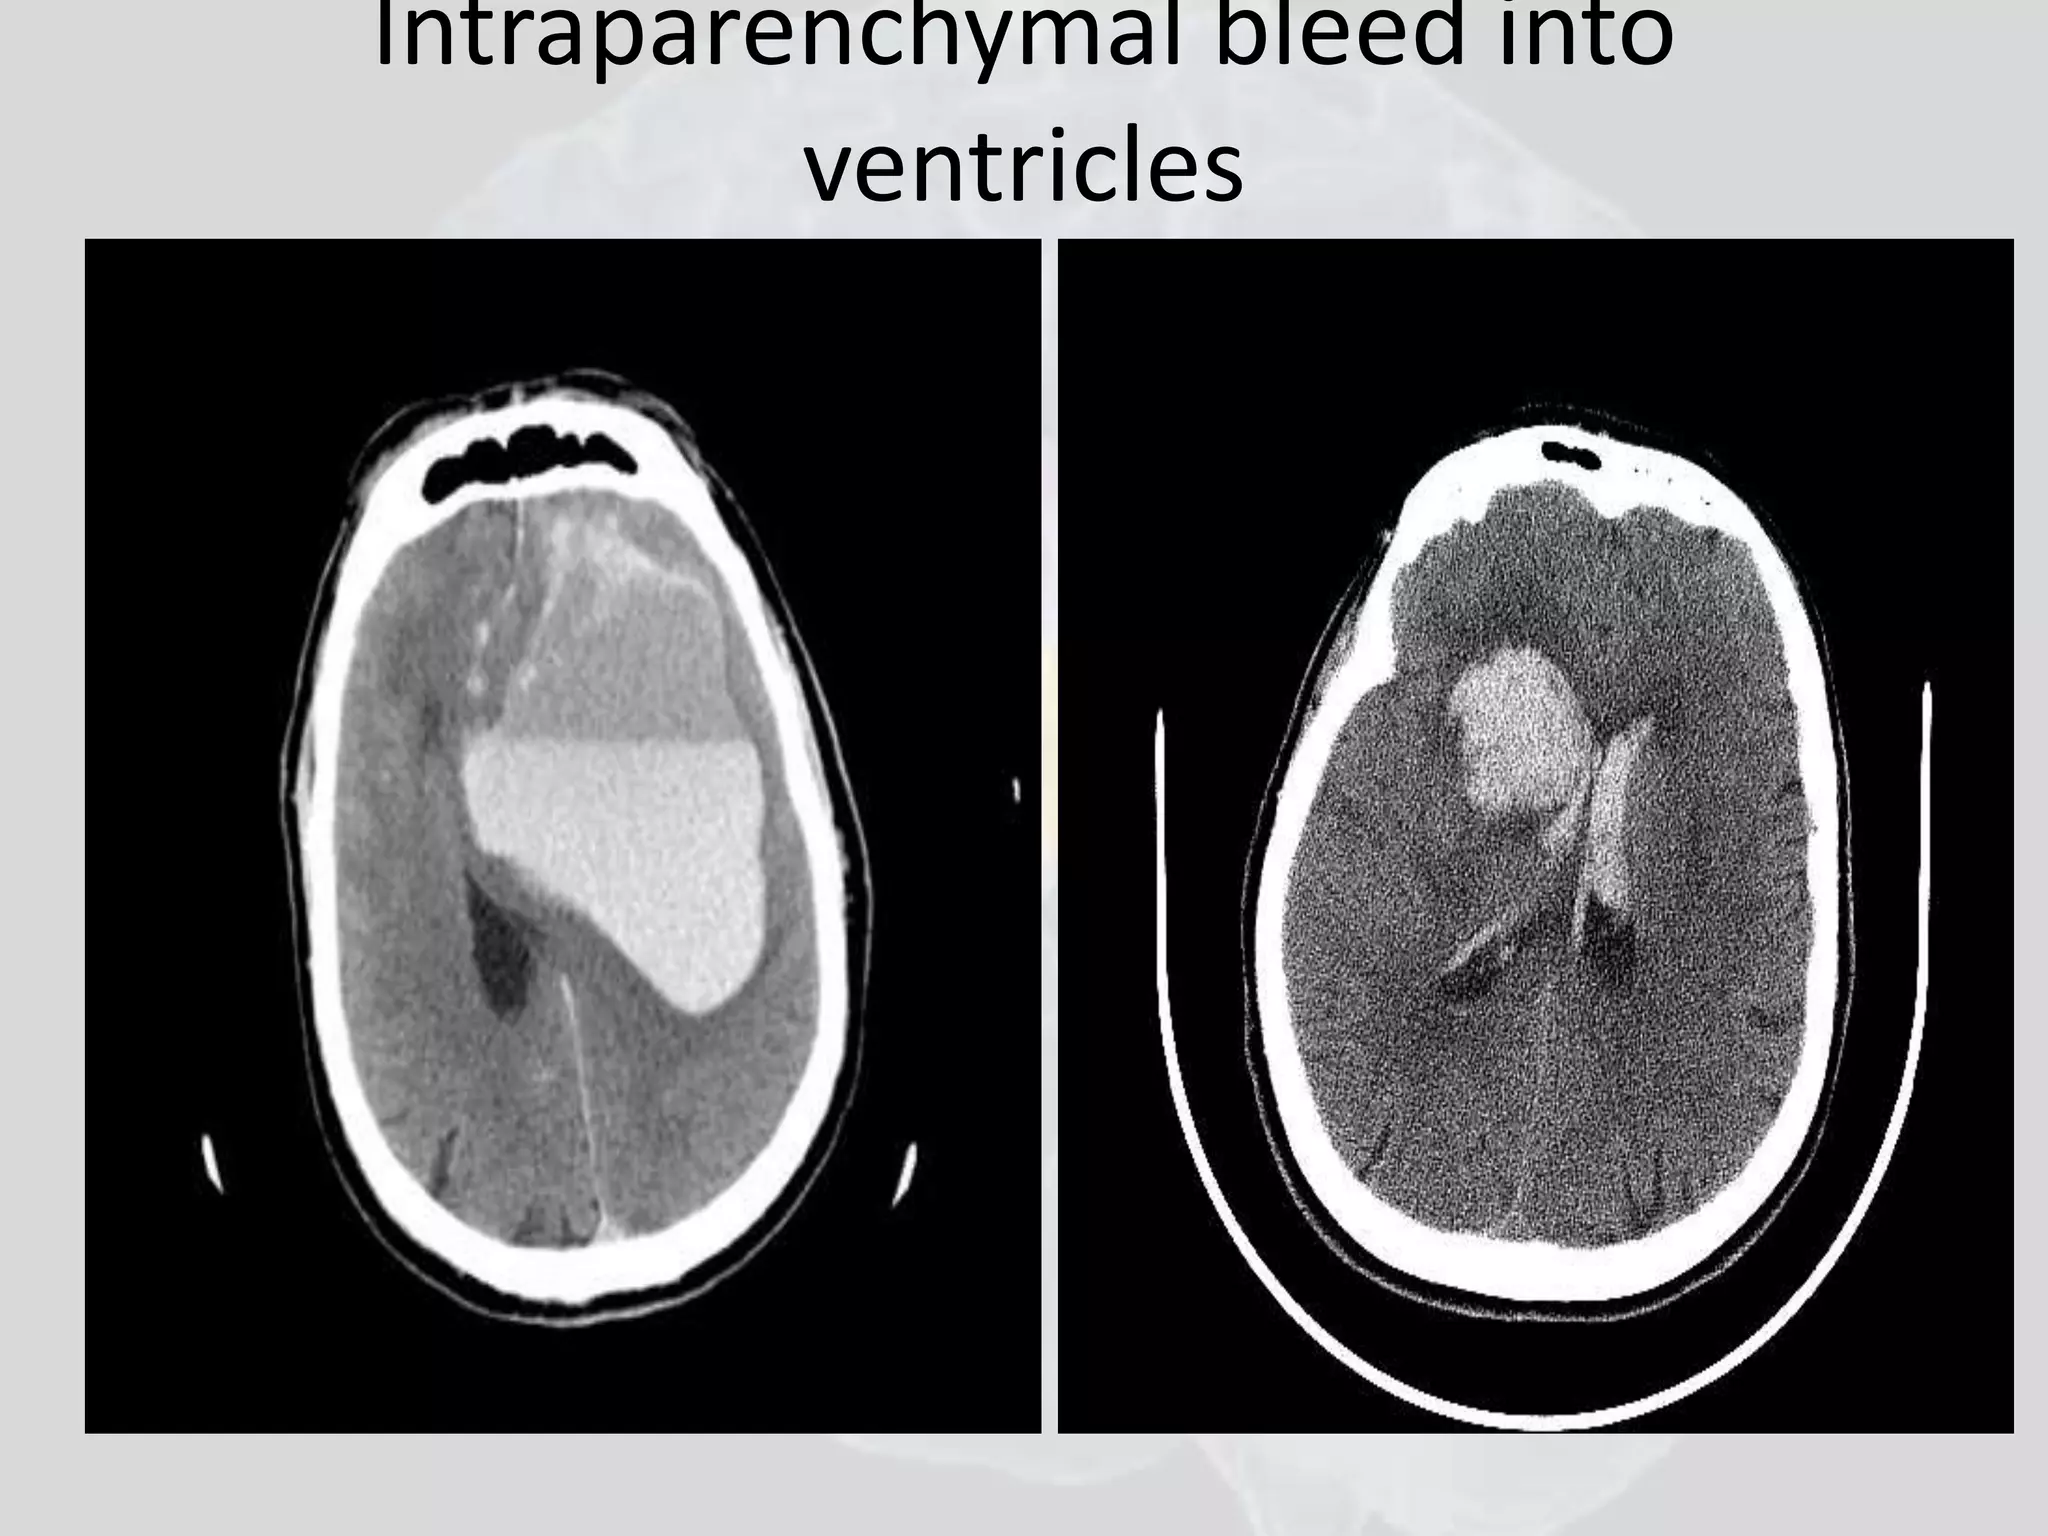

Stroke

• Intra parenchymal

• Subarachnoid heamorrhage

• Subdural heamatoma

• Epidural heamatoma

• Lacunar infarcts

• Ventricular bleed

Intraparenchymal bleed into

ventricles

Intraventricular bleed

Subarachnoid Hemorrhage Bloodshows white on CT. Anterior Communicating Artery aneurysm has burst, flooding the basal structures under the brain outside the brain parenchyma, but will occasionally empty into a Ventricle as it has on the left here (see fluid level). Note typical “bat wing” shape just above the mid-brain (green arrow).